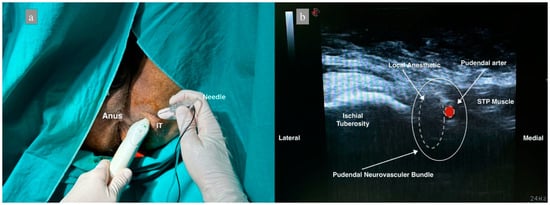

2.5. NS- and US-Guided Anterior Approach Bilateral PNB